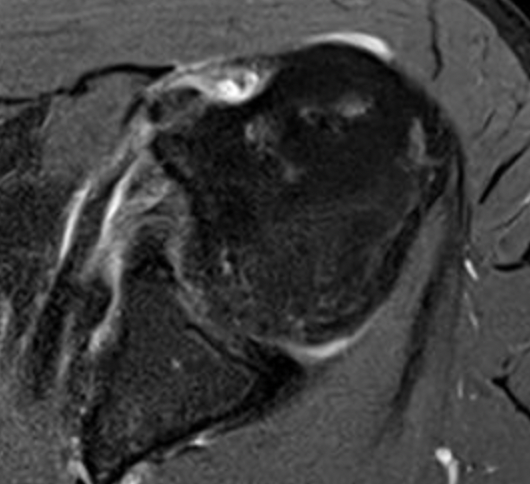

Full thickness retracted subscapularis tear

Full thickness retracted subscapularis tear with medial dislocation of long head of biceps tendon